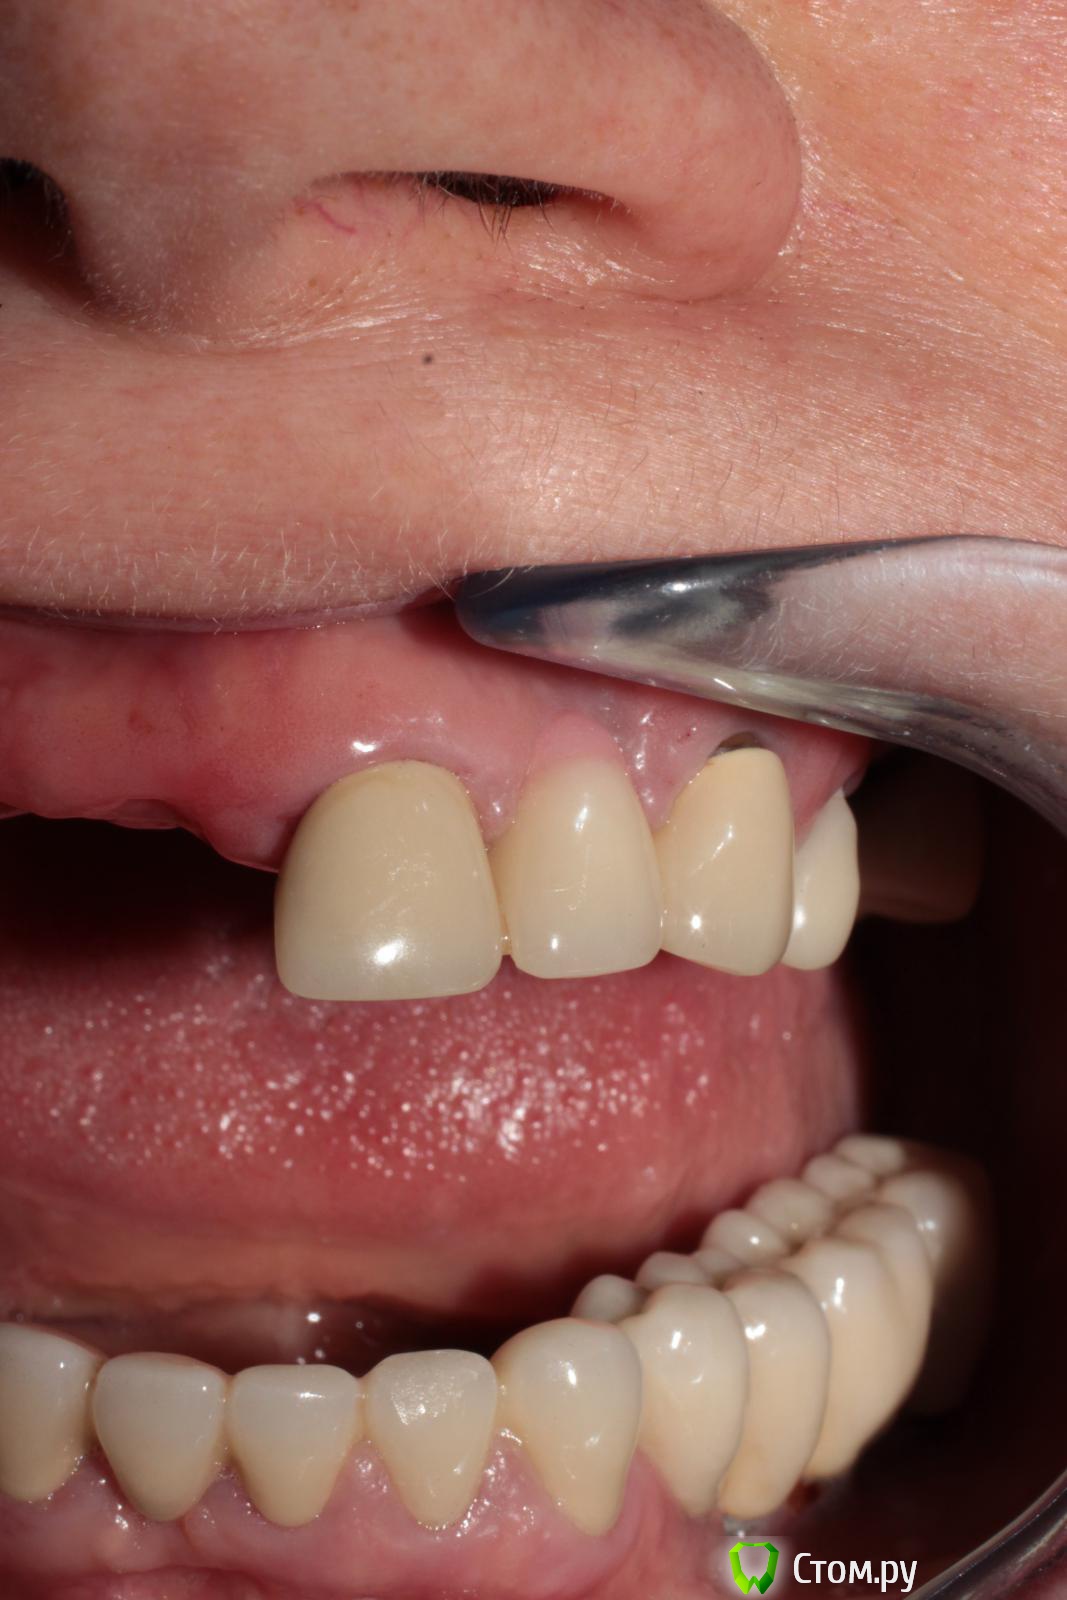

biv29 Опубликовано 30 апреля, 2014 Поделиться Опубликовано 30 апреля, 2014 (изменено) Уважаемые коллеги, прошу вашей помощи в составлении плана комплексной реабилитации пациентки.Пациентка 1962 г.р., 2 года назад были установлены имплантанты на н/ч, осуществлено протезирование (работал другой стоматолог-ортопед). Имеется вертикальная резорбция кости н/ч, рецессия десны, оголение имплантантов.На в/ч сохранены 17, 21, 23, 24, 27. Установлен ЧСПП. 21-23 МК-мостовидный протез (коронка 23 не доходит до десневого края). 24 - временная пластмассовая коронка.Имеется снижение высоты прикуса.- Я склоняюсь к следующему варианту работы:удаление 17, 21, 23, 24, 27; проведение синус-лифтингов с двух сторон, аугментация, установка имплантантов; временное протезирование на время реабилитации после операции, временное протезирование на пластмассовых коронках, постоянное протезирование МК.1. При этом плане возникает вопрос о временном протезировании сразу после хирургического вмешательства. Имплантолог против установки ПСПП на в/ч. Как поступить в этом случае? Использовать ли стабилизацию ПСПП и его фиксацию на мини-имплантантах? Достаточно ли будет мягкой подкладки на внутренней поверхности ПСПП?2. Считаете ли целесообразным осуществить протезирование сначала на в/ч без переделки орт. конструкций на н/ч? 3. 21, 23, 24 - стоит удалять или есть вероятность, что еще послужат? 4. Какой план протезирования вы бы предложили в данной клинической ситуации? Заранее спасибо за возможные ответы. Изменено 30 апреля, 2014 пользователем biv29 Ссылка на комментарий

biv29 Опубликовано 30 апреля, 2014 Автор Поделиться Опубликовано 30 апреля, 2014 1. Фото в прикусе сейчас есть только на моделях (см. вложение). При необходимости приглашу пациентку и сделаю дополнительно.2. Эстетика важна, но альтернативные варианты в пределах разумного можно обговорить. Главное неудобство для пациентки - съемный протез на в/ч. Ссылка на комментарий